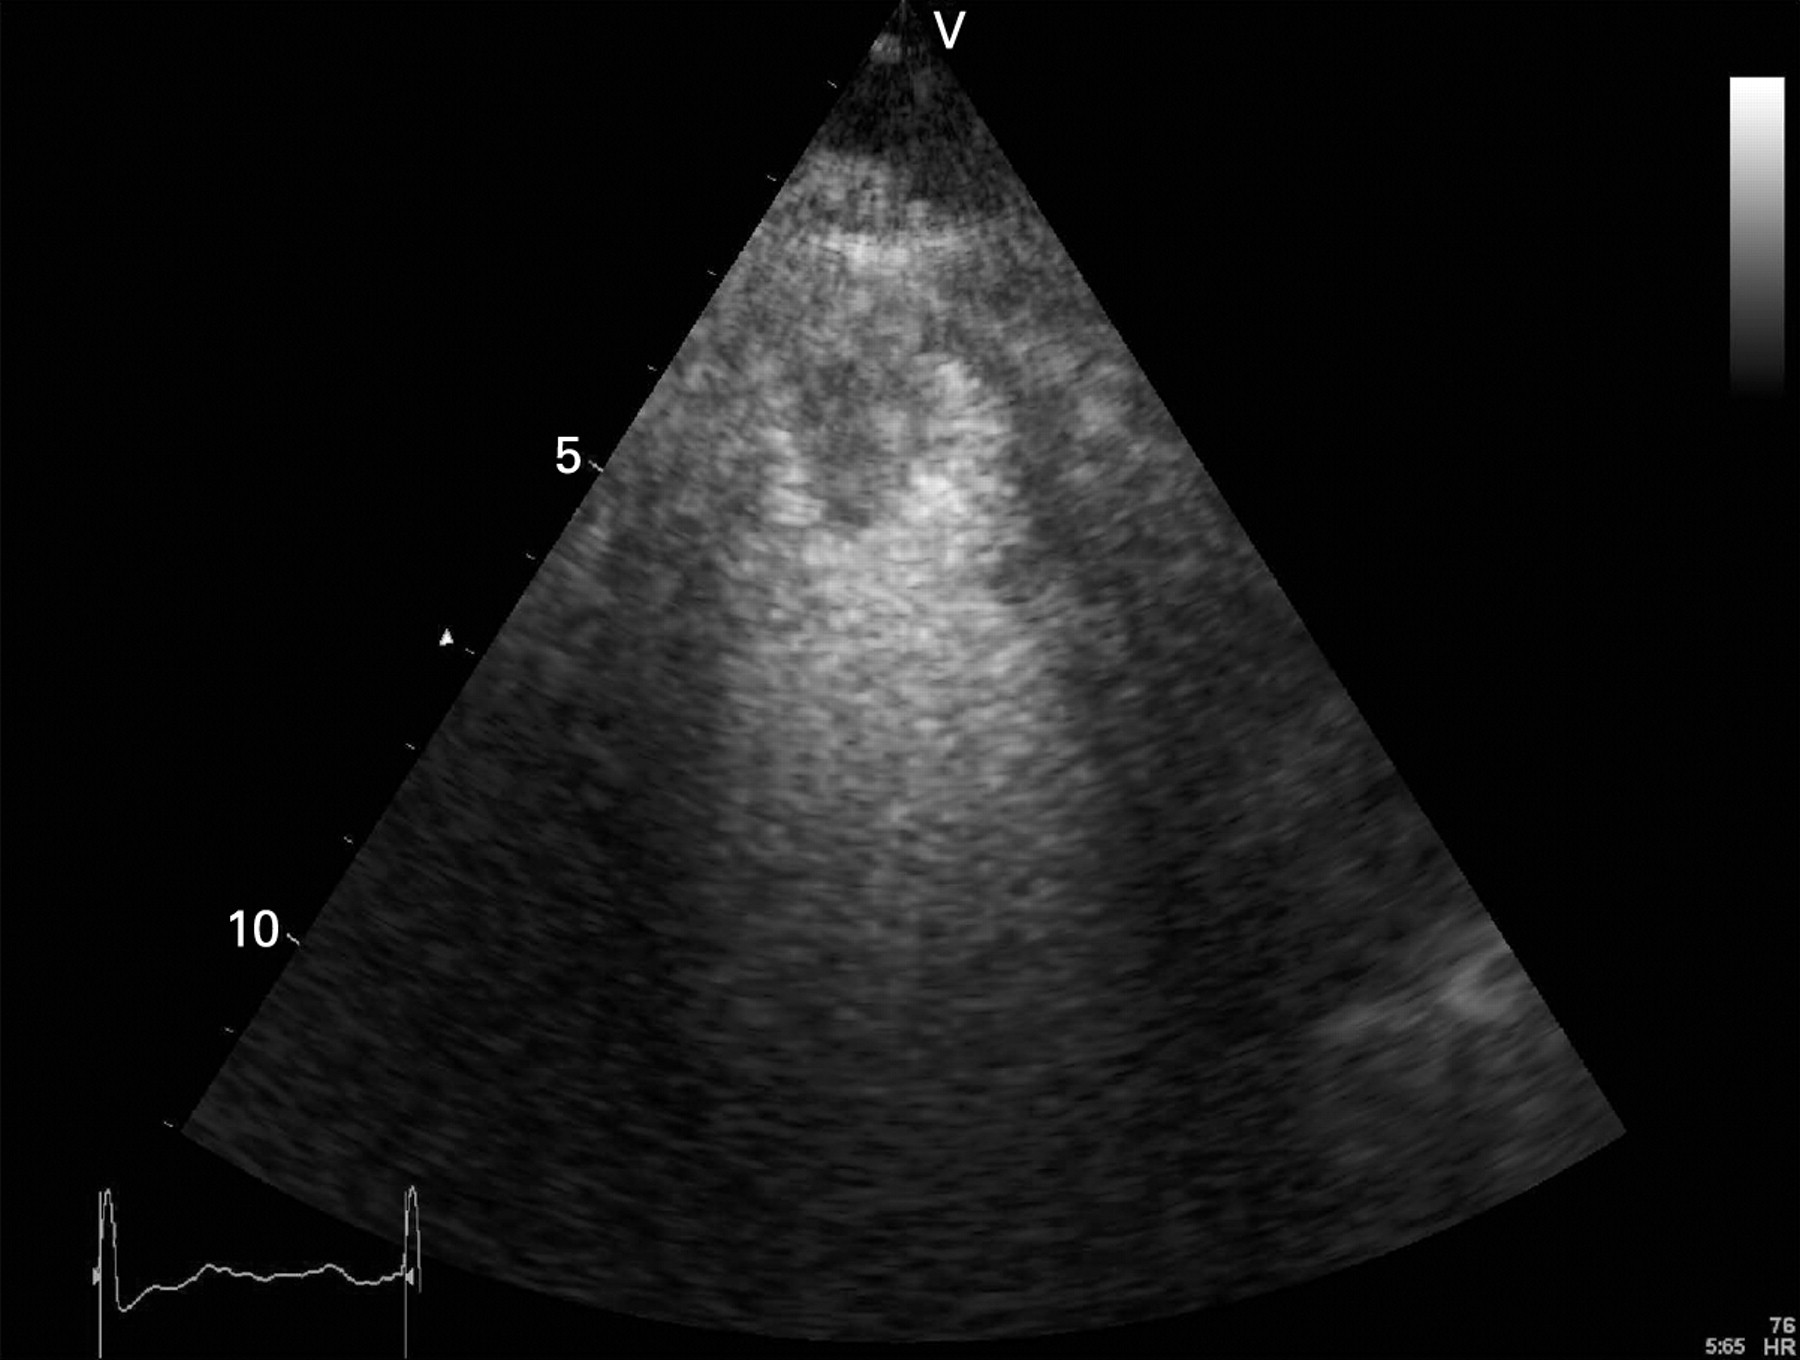

Эхокардиография является полезной методикой для стратификации риска и оценки прогноза после острого инфаркта миокарда. Показано, что для получения прогностической информации можно использовать множество традиционных эхокардиографических параметров, таких как объёмы и фракция выброса левого желудочка, индекс движения стенки, объём левого предсердия и наличие митральной регургитации. Разработка методов тканевой допплерографии и “speckle tracking” привела к появлению новых прогностических параметров, таких как деформация, скорость деформации и диссинхрония левого желудочка. Методика контрастной эхокардиографии позволяет оценивать перфузию миокарда и целостность микрососудистого кровоснабжения, предоставляет ценную информацию о жизнеспособности миокарда, тесно связанной с прогнозом. Стресс-эхокардиография позволяет выявить ишемию и жизнеспособный миокард, допплерография коронарных артерий — оценить резерв коронарного кровотока, и, наконец, трёхмерная эхокардиография даёт оптимальную информацию об объёмах, функции и сферичности левого желудочка, которые также являются важными параметрами долгосрочного прогноза.